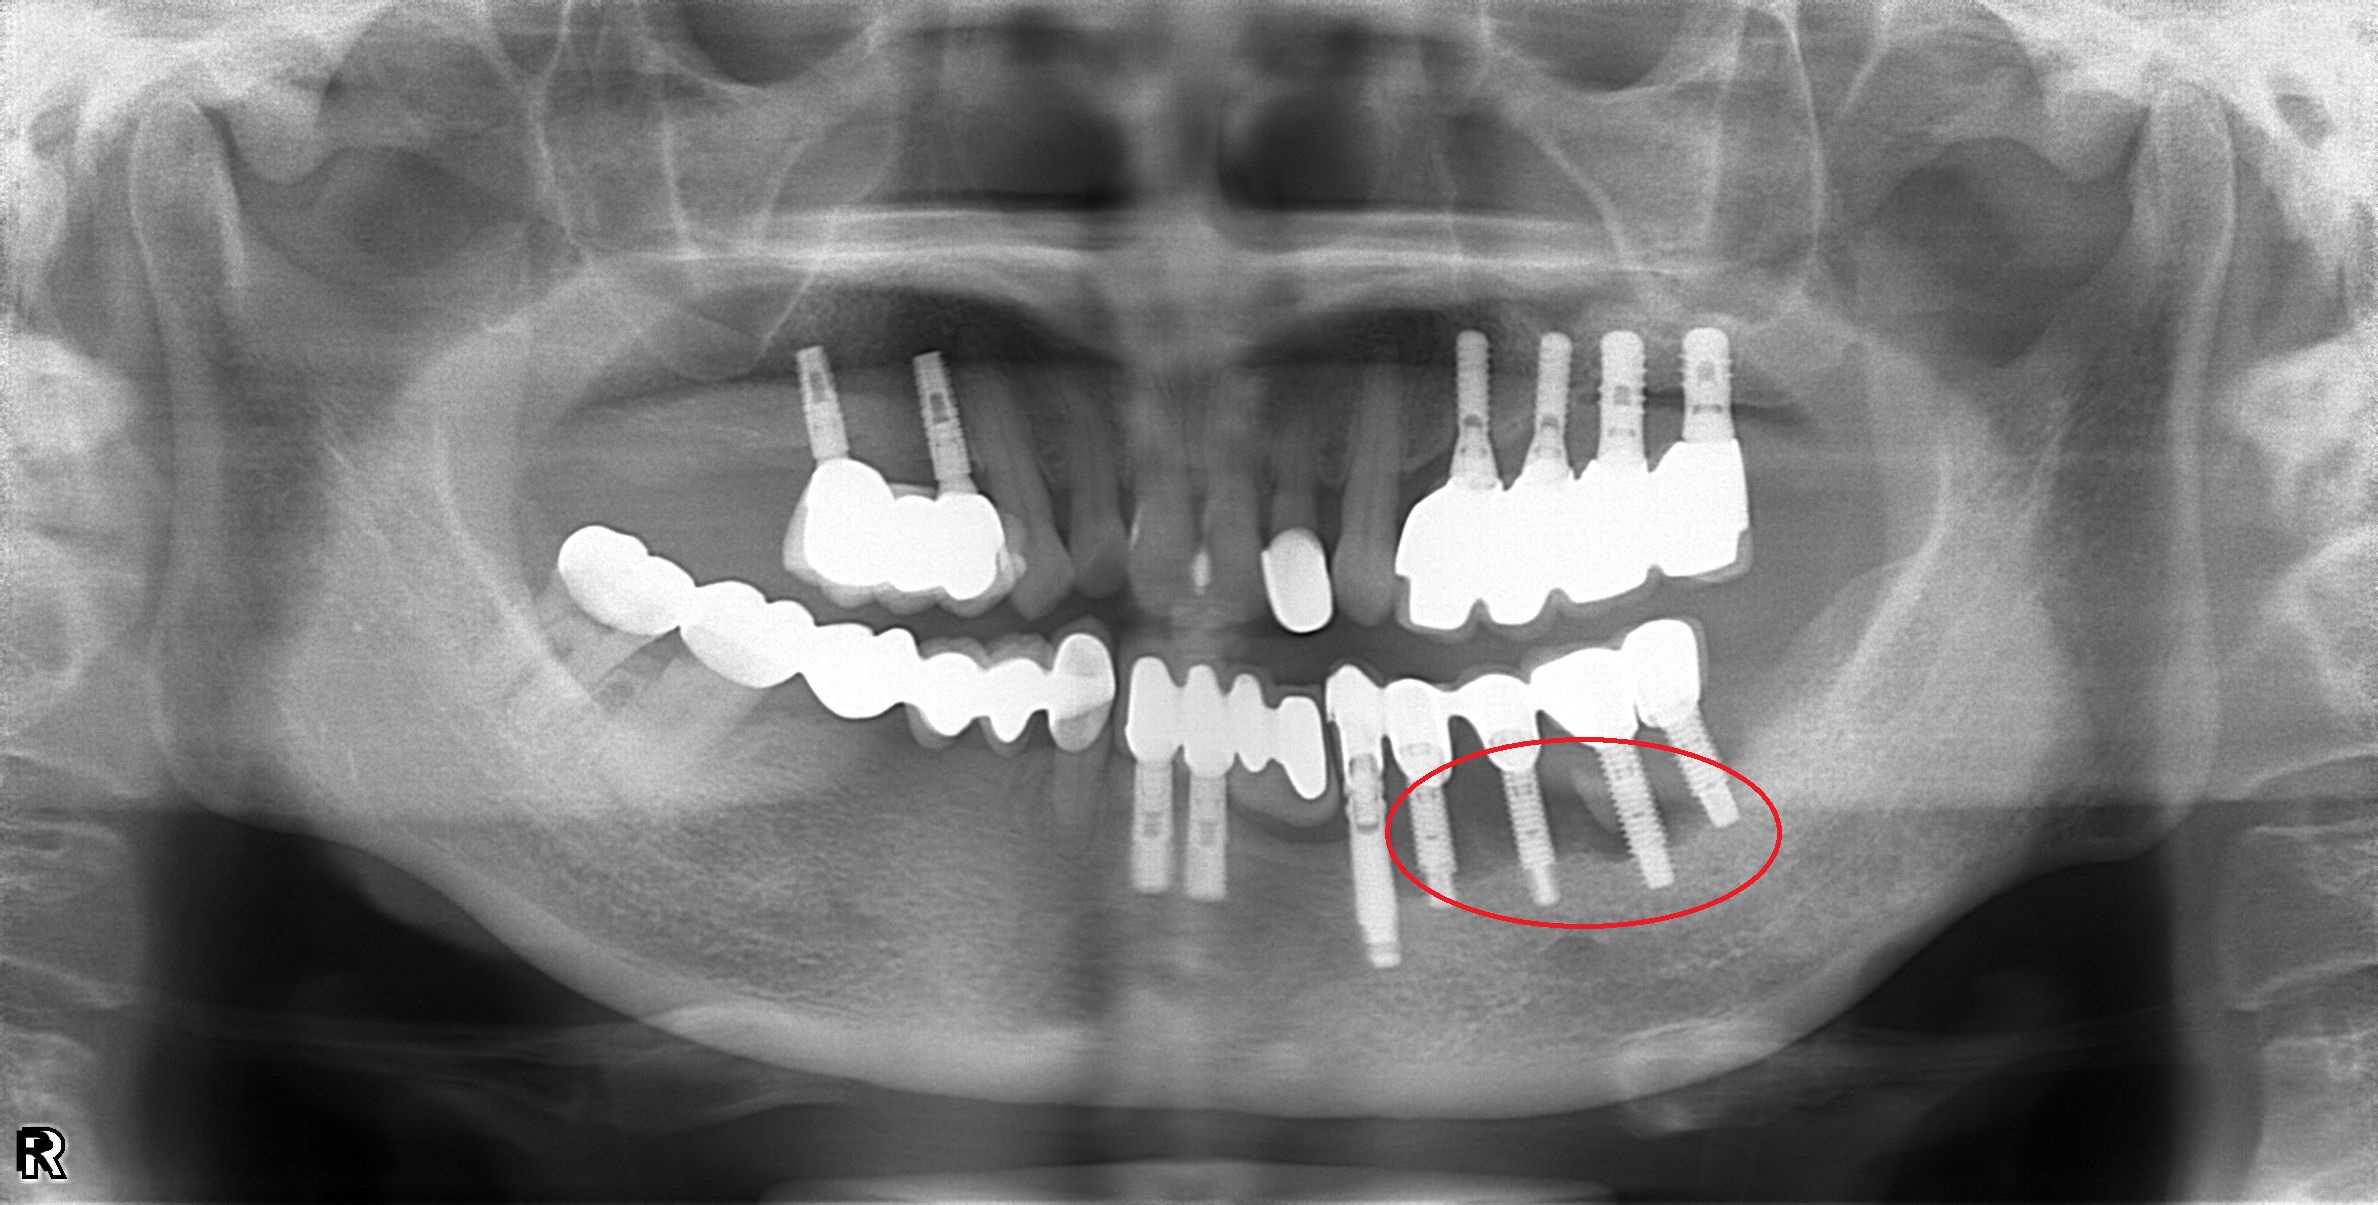

植體周圍炎處理

案例一